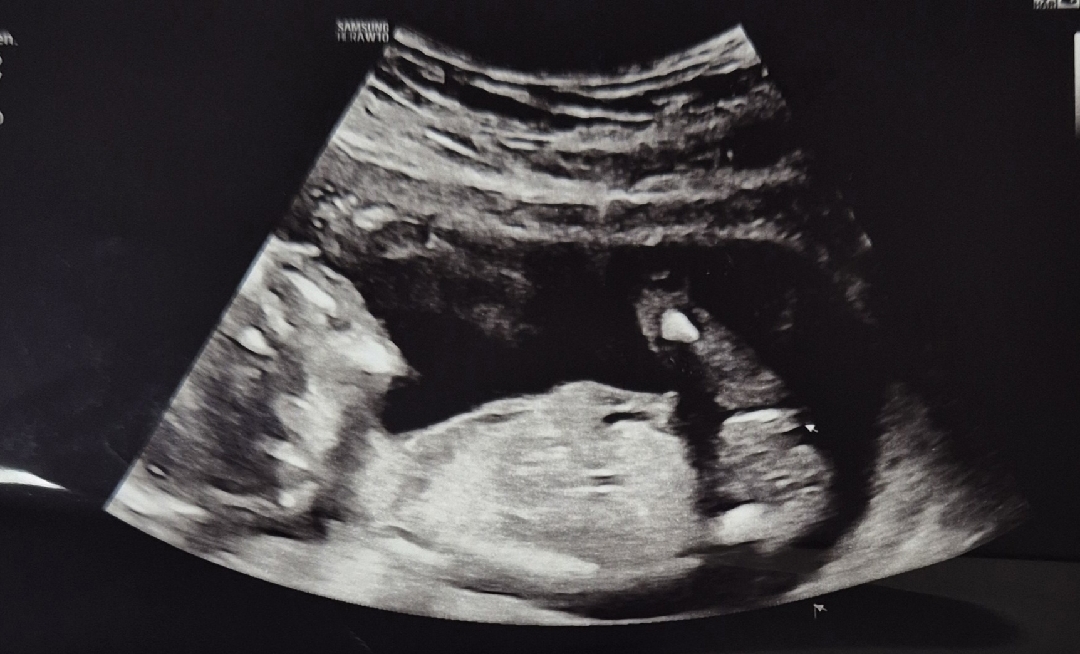

15주6일 진료보러갔는데 성별알려주신다더니 아기가 다리사이를 안보여주는데 옆으로 봤을땐 딸같아요 하셨는데 성별반전있을까요?? 저 화살표부위가 생식기라고 하셧어용